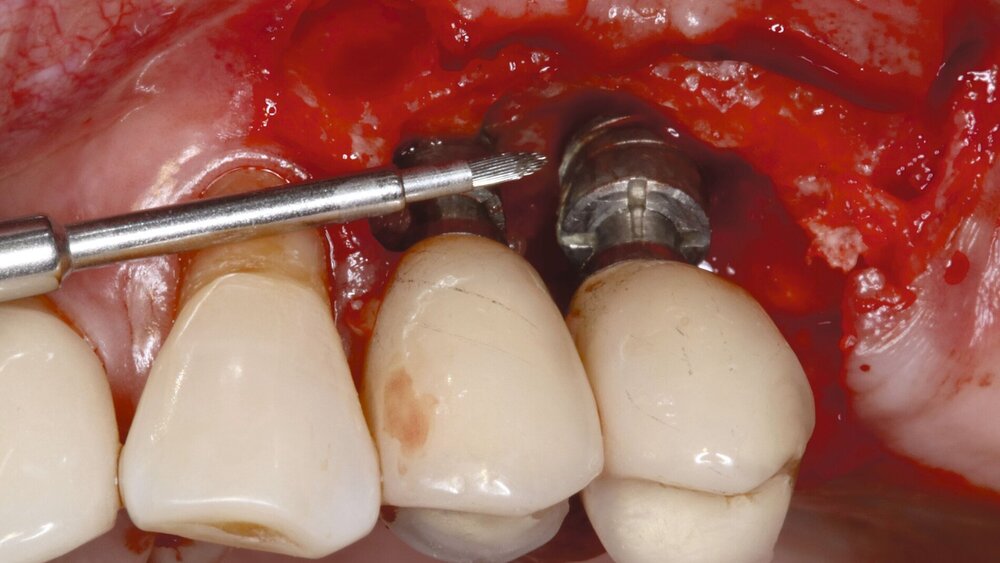

Die adjuvante antimikrobielle Photodynamische Therapie (aPDT) soll helfen, im Rahmen der subgingivalen Instrumentierung (Therapiestufe 2) und der Unterstützenden Parodontaltherapie (Therapiestufe 4) die antimikrobiellen Effekte der mechanischen Plaqueentfernung zu verstärken. Dazu werden photosensibilisierende Substanzen in Kombination mit Laserlicht eingesetzt, um Bakterien lokal in der Tasche zu zerstören. Ob dieser Mechanismus jedoch zu klinisch relevanten Effekten führt, ist unklar.

Die Arbeitsgruppe um Jervøe-Storm hat nun die aktuelle Literatur bis zum 14. Februar 2024 gesichtet. In die Auswertung einbezogen wurden randomisierte kontrollierte Studien (RCTs) (sowohl paralleles Gruppen- als auch Split-Mund-Design) mit Teilnehmern mit einer klinischen Diagnose von Parodontitis und Periimplantitis. Verglichen wurde die gleichzeitige Anwendung der aPDT nach subgingivaler oder submukosaler Instrumentierung (SI) im Vergleich zu SI allein oder einer Kombination von SI und einem Placebo-aPDT.